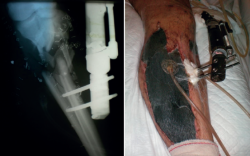

5. Colocación de un sistema de presión negativa de tipo Vacuum Assisted Therapy (VAC®), el cual se cambia cada 48 horas (Figura 2).

retla.05210.fs2209019-figura2.png

Figura 2. Radiografía y fotografía clínica de la asistencia en el ROLE 2: desbridamiento, fijador, fasciotomía y sistema VAC®, repitiéndose el desbridamiento y el cambio de VAC® cada 48 horas.